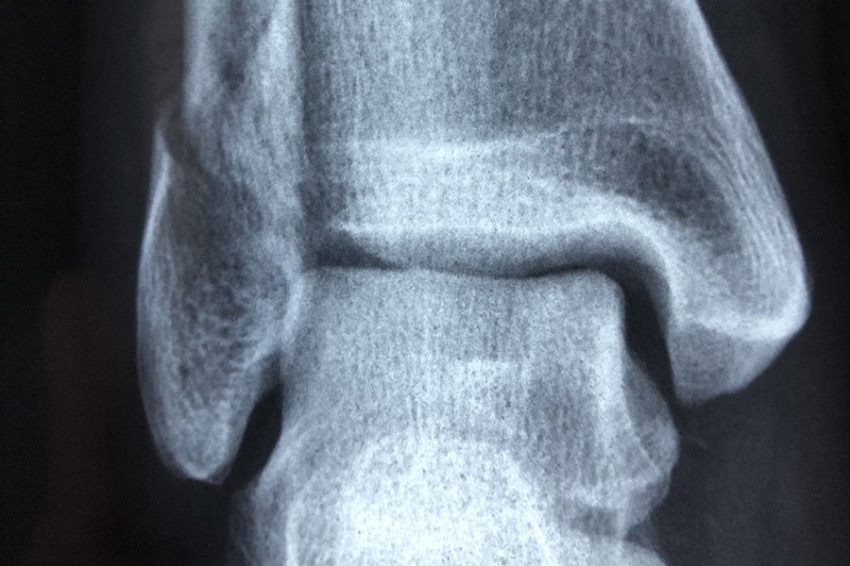

На ежегодном собрании Радиологического общества Северной Америки (RSNA) были презентованы итоги нового исследования, показавшего, что диета с высоким содержанием ультрапереработанных продуктов провоцирует накопление жира в мышцах бедра. А далее следует рост рисков остеоартрита коленного сустава.

Аналитика показала: у тех, кто часто включал в свой рацион подобную пищу, фиксировали больший объем жира в мышцах бедер, что способствовало развитию остеоартрита. Связь прослеживалась даже при небольшом объёме потребляемых калорий и определённом уровне физической активности.

Изменение пищевых привычек, как рекомендуют учёные, станет важным шагом в профилактике и лечении остеоартрита.